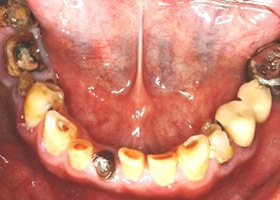

病患:55歲先生。

主訴:多顆缺牙,想全口治療。

多顆缺牙、牙周病、多顆蛀牙。

治療前

多顆缺牙及牙周病、蛀牙

proimages/Case/dentalimplant/10/02/before02.jpg